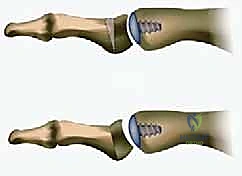

- ما هي؟ الإجراء "الذهبي التقليدي" لتخفيف الألم. يتم إزالة الغضروف المتبقي، وتثبيت عظام المفصل معاً باستخدام مسامير أو شرائح معدنية حتى تلتحم العظام وتصبح عظمة واحدة صلبة.

- العيوب: يقضي على الألم بنسبة 100%، ولكنه يقضي على حركة المفصل تماماً. المريض لن يتمكن من ثني إبهامه أبداً، مما يمنع الجري السريع، القرفصاء، وارتداء أحذية الكعب العالي.

3. استبدال المفصل (Arthroplasty) - الثورة الطبية

- لمن تصلح؟ للمرضى في المراحل المتقدمة (2، 3، وأحياناً 4) الذين يرفضون دمج المفصل ويرغبون بشدة في الحفاظ على حركة المفصل.

- ما هي؟ استبدال أسطح المفصل التالفة بمواد صناعية. وهنا تبرز التقنية الأحدث والأكثر نجاحاً عالمياً: **تقنية Arthrosurface